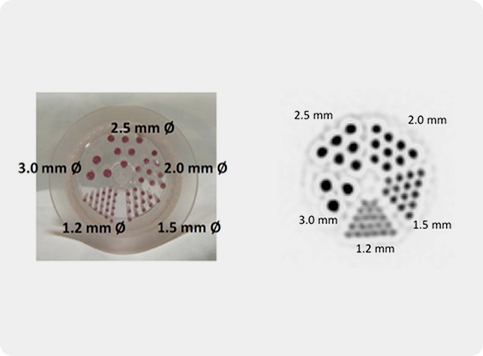

Several crystal-APD units and the corresponding frontend electronics are assembled in detector modules. Our APD-based detector module has 384 LYSO 2x2x20 mm crystals and covers a detection area of ~4x8 cm. One of the advantages the APDs is the capability of performing the double readout of the scintillation crystals, which allows to calculate the DoI of the detected photons. Associated to the fine detector pitch (2x2 mm) and the one-to-one coupling between crystal and APD pixels, the DoI capability permits an excellent spatial resolution of the order of 1.3 mm over the whole Filed-of-View.

The main spectroscopic characteristics of the Clear-PEM system are energy resolution for 511 keV photons of of 13.4%, coincidence time resolution of 2.8 ns (FWHM) and DoI resolution of 2.8 mm (FWHM).

Clear-PEM double readout scheme allows calculation of photon Depth of Interaction (DOI) and compensates blurring due to the parallax effect in PET resulting in an isotropic image resolution of 1.3 mm FWHM.